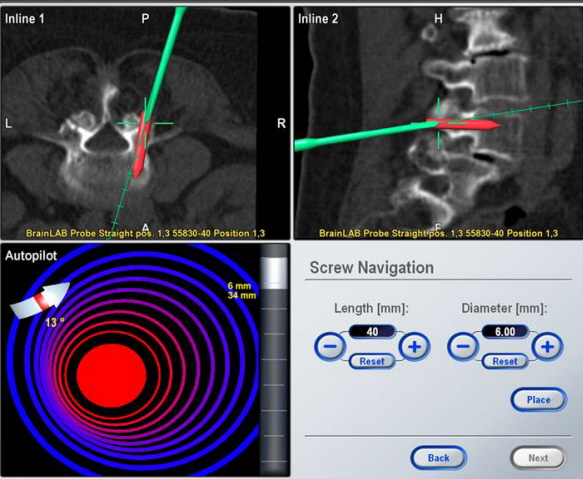

patients. The length and diameter of the screws was noted. A

reference frame was attached to the spinous process of each

vertebra and virtual image of vertebra was obtained (Fig -1) and

the registration was performed using the standard techniques

1, 8, 11.

For pedicle screw placement in which minor deviation in the

screw trajectory may result in a pedicle perforation, a CT-based

image-guidance system provides the surgeon with a view of the

pedicle and surrounding structures in multiple planes (Fig 5).

For each pedicle, an ideal entry point and trajectory for screw

placement may be chosen. An image-guidance system is able to

track and provide updated information about the location of the

probe to avoid injury to the spinal cord 3, 15, 16.

Real time imaging also helps to place longer and thicker screws

without the fear of violating the anterior cortex and increased

surgical confidence (Fig 6).